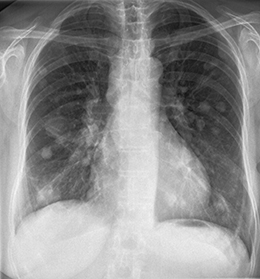

Röntgenuntersuchungen finden breite Anwendungen. Sie dienen u.a. zur Darstellung von Knochen und Gelenken nach Verletzungen, zur Beobachtung des Heilungsverlaufes nach Brüchen und Gelenkersatz, zur Beurteilung der Verschleißerscheinungen bei Arthrose, zum Nachweis von Tumoren (Mammographie), sowie zur Erfassung des Zustandes kranker Zähne. Sie werden auch zur Beurteilung der Lunge, des Bauches, zur Darstellung von Tränen- und Speicheldrüsen sowie zur Kontrolle der Nahrungspassage in der Speiseröhre und im Magen-Darmtrakt eingesetzt.